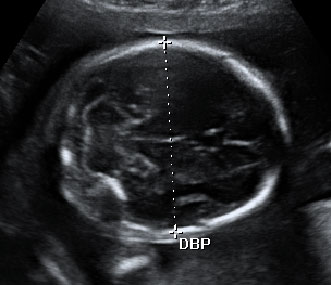

En esta ecografía en 4D se distingue el escroto de este feto varón. En la ecografía de la 20 semanas de embarazo, es muy probable que la embarazada ya sepa el sexo de su bebé, ya que se puede ver en la semana 12. No obstante, ahora se confirma.

Ultrasonido del aparato genital masculino en tres dimensiones

Las imágenes dan buena cuenta del sexo del bebé: se aprecia la pierna, el escroto, el pie y el cordón umbilical de la criatura.